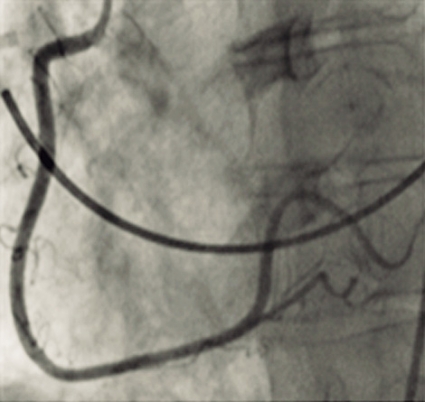

Vid ankomsten till sjukhuset var patienten smärtpåverkad, systoliskt blodtryck var 90/60 mm Hg, puls 96/min, och i status noterades dyspné och rassel över lungorna. EKG visade dålig R-vågsprogression, ST-sänkningar och T-vågsnegativitet (Figur 1).